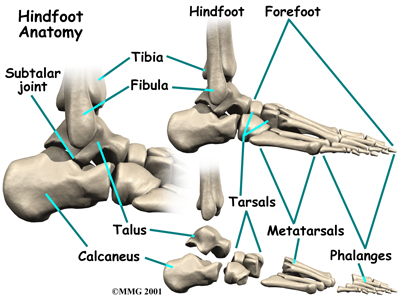

The skeleton of the foot centers around the talus, or ankle bone, which forms the main part of the ankle. The two bones of the lower leg, the large tibia and the smaller fibula, come together around the talus to form a very stable structure.

The two bones that make up the ‘hindfoot’ include the talus and the calcaneus, or heel bone. The talus is connected to the calcaneus at the subtalar joint. The ankle joint where the talus connects to the tibia and fibula allows the foot to bend up and down. The subtalar joint allows the foot to rock from side to side.

Just down the foot from the ankle is a set of five bones called tarsal bones that work together as a group. These bones are unique in the way they fit together. There are multiple joints between the tarsal bones. When the foot is twisted in one direction by the muscles of the foot and leg, these bones lock together and form a very rigid structure. When they are twisted in the opposite direction, they become unlocked and allow the foot to conform to whatever surface the foot is contacting.

The tarsal bones are connected to the five long bones of the foot called the metatarsals. The two groups of bones are fairly rigidly connected, without much movement at the joints.